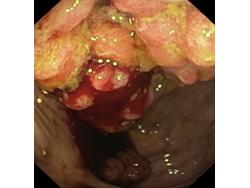

Nowotwory przewodu pokarmowego